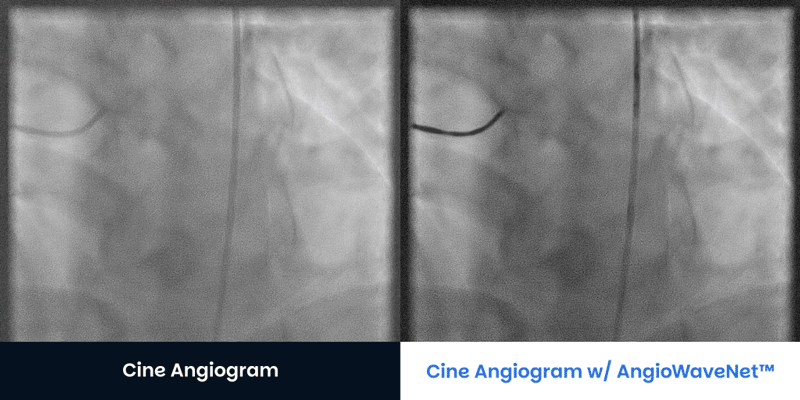

Large Patients BMI > 40 Contact UsGet a Demo CTO Patients Angiograms courtesy of:Jaikirshan Khatri, M.D., Hassan Saleh, M.D. and Weill Cornell Medical Center Left anterior oblique 27°, cranial 1° (unprocessed on left, processed on right) Left anterior oblique 31°, caudal 33° unprocessed on left, processed on right Right anterior oblique 2° caudal 33° (unprocessed on left, processed on right) Right anterior oblique 13°, caudal 36° unprocessed on left, processed on right Contact UsGet a Demo Diagnostic Cine Angiograms Contact UsGet a Demo